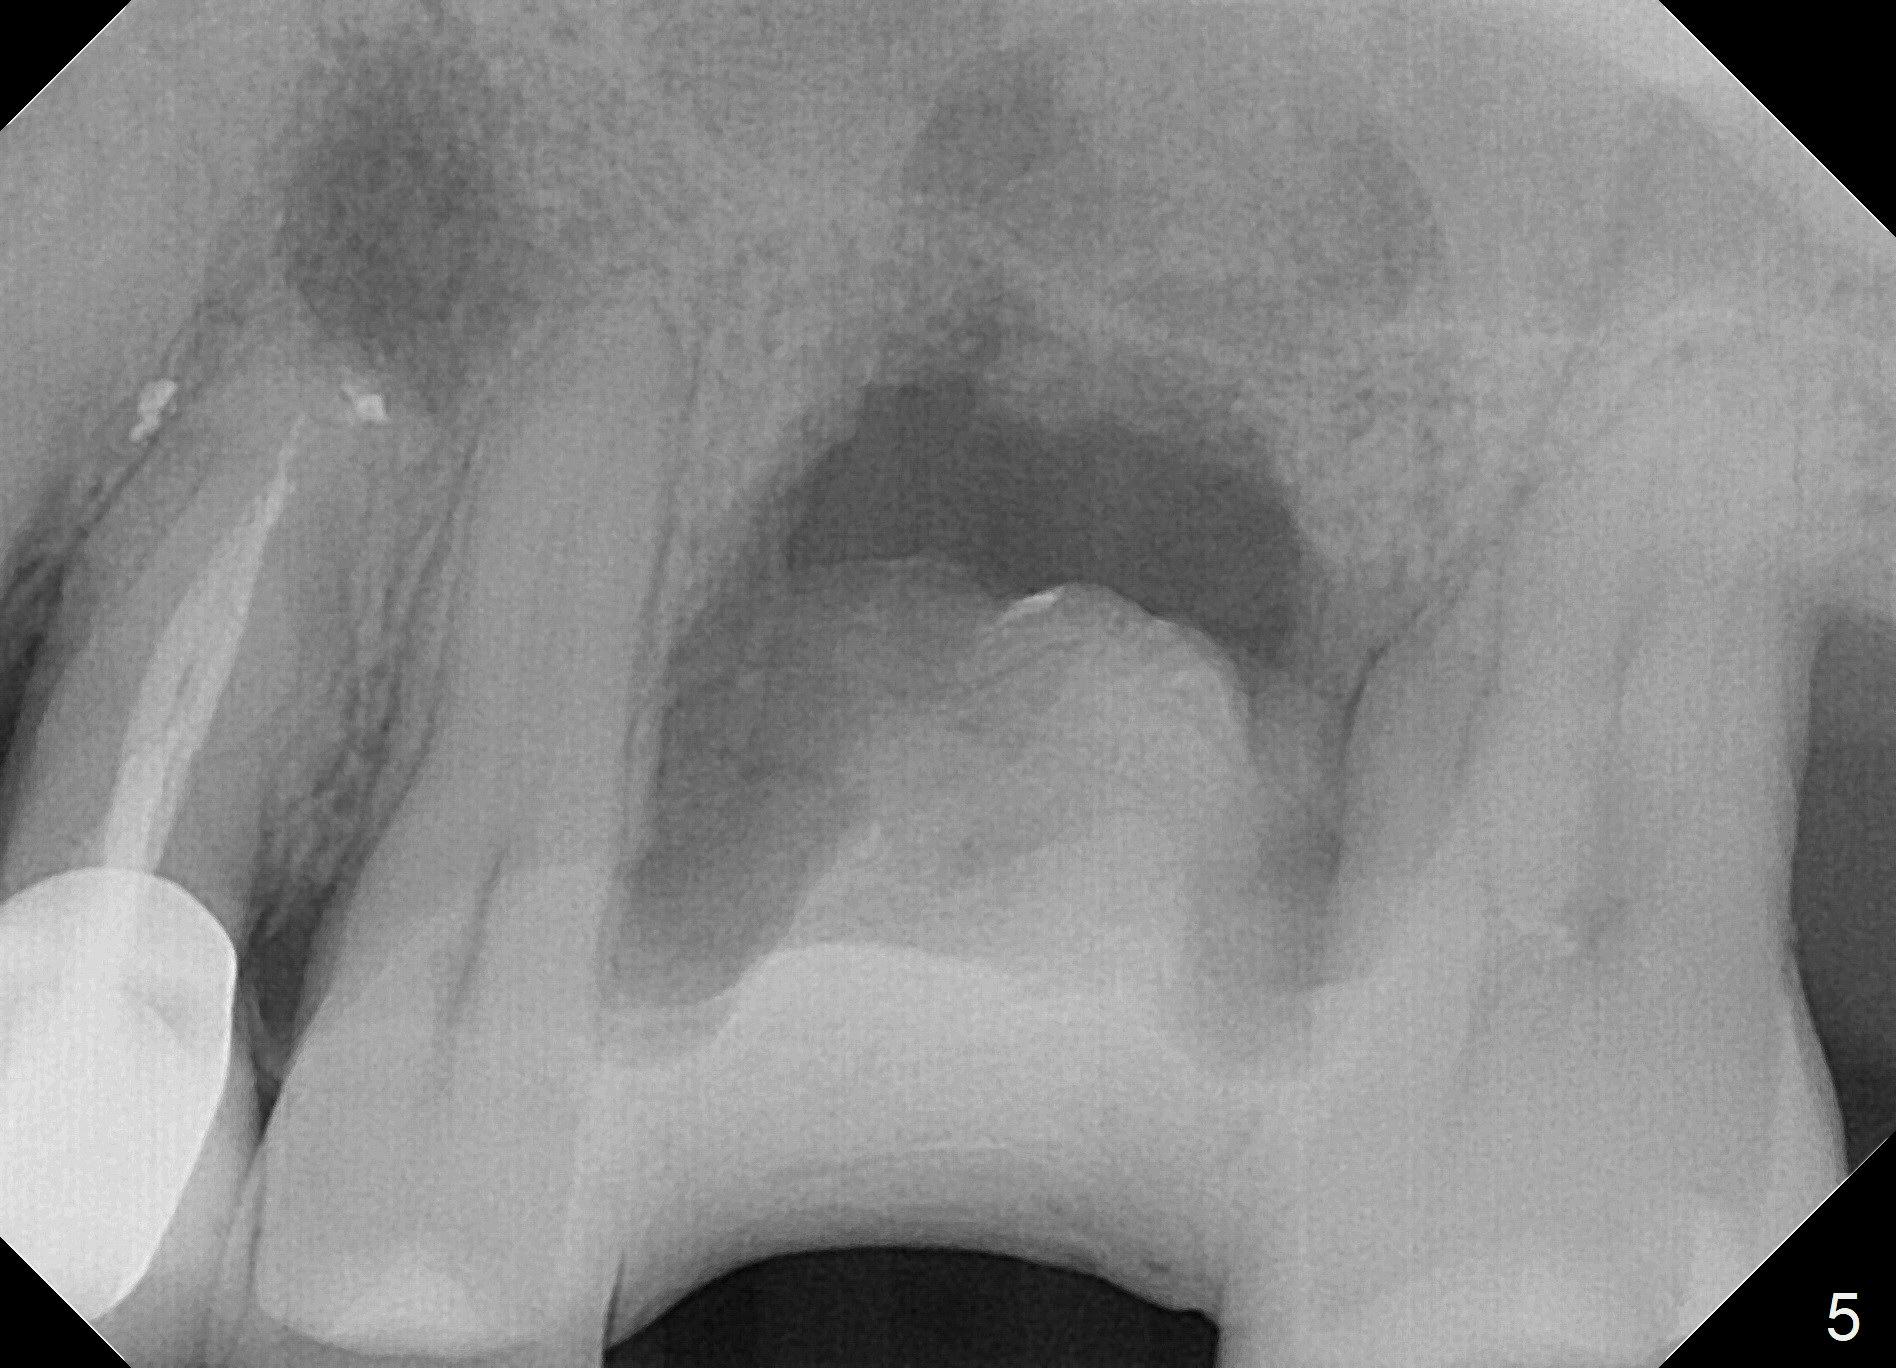

When the tooth #14 is extracted, the buccal plate is lost, while the apex of the palatal socket is perforated. The palatal slope of the septum appears to be a suitable site for osteotomy, but the depth seems to be 2 mm. After sequential osteotomy until 5.3 mm with drills, a 5.9 mm SM tap obtains stability (Fig.2). A 5.9x8 mmm implant is placed with barely sufficient stability after 1 piece of PRF membrane and VeraGraft (Fig.2-4). The implant rotates and dislodges when an abutment is being placed. Neither do 6-8x17 mm Tatum taps achieve primary stability. Socket preservation is performed, followed by periodontal dressing (Fig.5). Primary stability might have been obtained if a smaller IBS implant with fins were placed in the palatal socket. The periodontal dressing has dislodged 1 week postop; the socket appears healing (Fig.6,7). Bone graft seems to be minimal or bone density of the graft is low (Fig.8). The socket heals with a wide ridge 2 months post socket preservation, but the tooth #15 seems to be buccal (Fig.9) and mesial (Fig.10) shift. After use of Magic Split and Expanders (until 3.8 mm for 13 mm), try 5 mm dummy implant (Fig.11). If 6 mm one fails to achieve stability substantially, switch to 7 mm Tatum tapered tap provided there is enough mesiodistal space (use 8 mm implant positioner to gauze the space beforehand (preop)). Consider using Vanilla (not Vera) Graft to fill in the gap between implant and osteotomy. When primary stability is obtained, place a nonfunctional provisional to prevent further shifting (Fig.11 white outline). After osteointegration, use the provisional (reline and separator) to distalize the tooth #15.